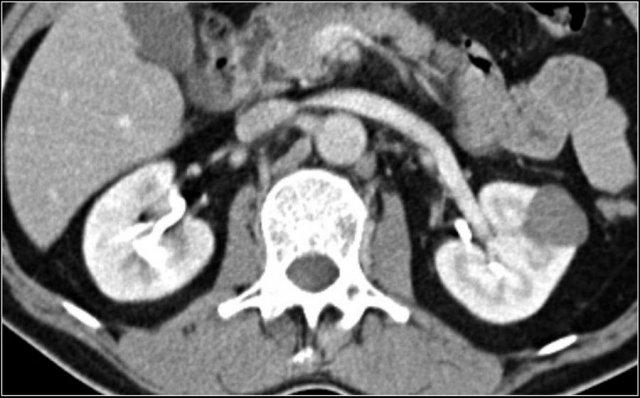

TCC khó phát hiện trên hình ảnh CT không tiêm thuốc cản quang.

Thì thận sinh (nephrogenic phase) là thì tối ưu để thấy rõ ranh giới giữa TCC và nhu mô thận bình thường có ngấm thuốc.

Hình ảnh thì bài tiết cho thấy các bất thường của hệ thống đài bể thận như đài thận giãn, đài thận bị khối u lấp đầy hoặc đài thận không ngấm thuốc do khối u thâm nhiễm.

TCC là tổn thương điển hình dạng hạt đậu (xem hình).